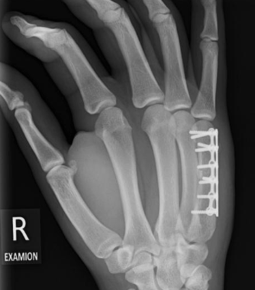

Mittelhandfraktur Am Daumen Handchirurgie

Konservative Und Operative Therapie Von Mittelhandfrakturen